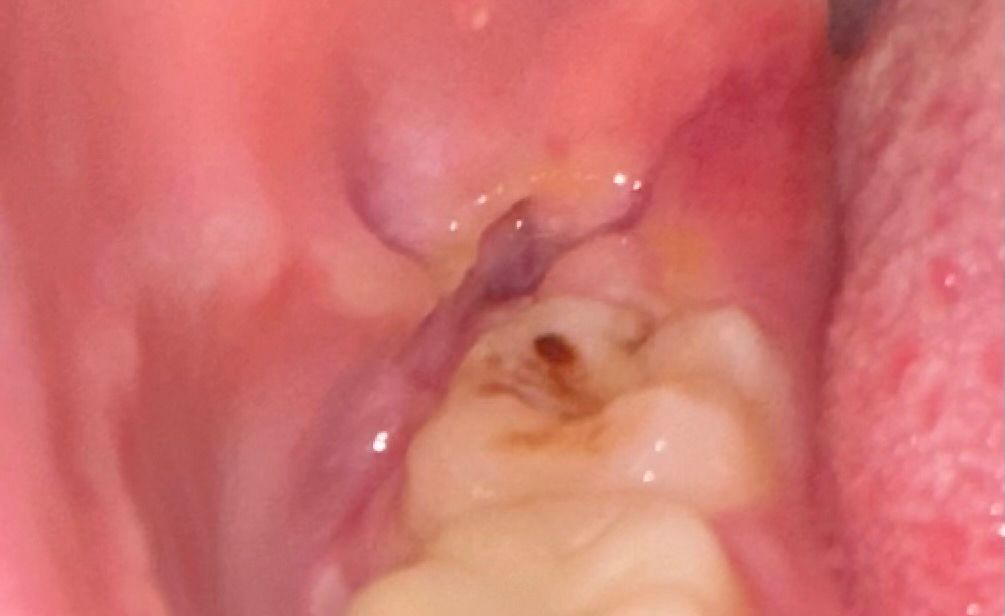

사랑니 발치 후 어금니에 무언가 보이는데…충치가 생긴건가요? 아니면 양치가 덜 된 것일까요?

ㅠㅠ 양치를 잇몸에 제대로 해도 되는건지.., 드라이소켓이 연관검색어로 계속 떠서… 괜찮은건지 궁금

ㅁ합니다

현재 사진으로는 정확한 판단이 어렵습니다. 우식으로 인하여 나타난 모양일 수도 있으며, 출혈이 치아의 교합면에 놓여서 보이는 사진일 수도 있어 보입니다. 정확한 것은 치과 방문 후 x-ray 및 임상검사를 해보아야 할 것으로 보입니다. 전체적인 검진을 한 번 받아보시길 바랍니다.

사랑니 발치 후에도 그 앞쪽 어금니 양치는 잘 해주셔야 합니다. 음식물인지 충치인지 임상사진만으로는 정확한 평가가 불가능합니다.

어금니에 검은 부분은 충치로 의심되며, 양치시에 발치한 구멍에 음식물 찌꺼기가 남지 않도록 충분히 가글하여 관리하여 주길 권합니다.

사진으로 봤을 경우에는 어금니 위쪽에 무언가 있어 보입니다. 발치를하고 생긴 조직일 수도 있고 충치일 수도 있습니다. 자세한 확인을 위해 치과에서 진료를 받아보는 것을 권유드립니다

1. 드라이소켓의 양상은 아닌것으로 보입니다

2. 옆 어금니는 충치일수도 있고 단순 착색일 수도 있을 것 같습니다